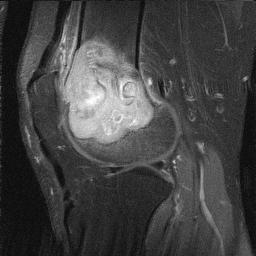

MRI

Low signal intensity T1 / high signal intensity T2

Areas of ABC seen in 10 - 14%

Look for signs of grade III: soft tissue extension

Imaging

Grade III with cortical destruction and soft tissue extension